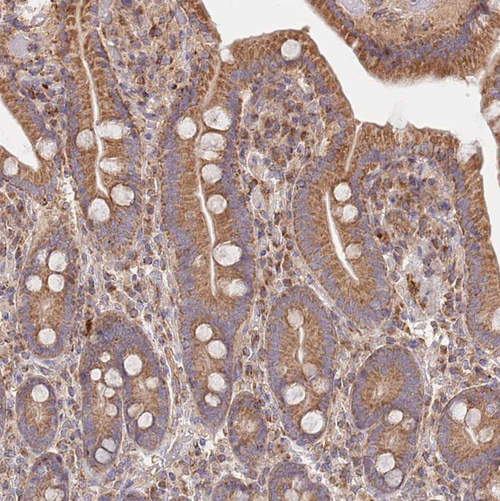

Immunohistochemical staining of human cerebral cortex shows moderate to strong cytoplasmic positivity in neurons.